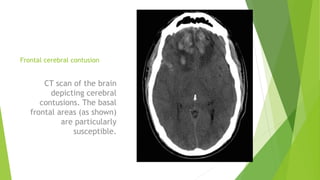

Frontal cerebral contusion

CT scan of the brain

depicting cerebral

contusions. The basal

frontal areas (as shown)

are particularly

susceptible.

Frontal cerebral contusion CTscan of the brain depicting cerebral contusions. The basal frontal areas (as shown) are particularly susceptible.

• #9 Focal cerebral contusions are the most frequently encountered lesions. Contusions are commonly seen in the basal frontal and temporal areas, which are susceptible due to direct impact on basal skull surfaces in the setting of acceleration/deceleration injuries. Coalescence of cerebral contusions or a more severe head injury disrupting intraparenchymal blood vessels may result in an intraparenchymal hematoma. &amp;lt;number&amp;gt;